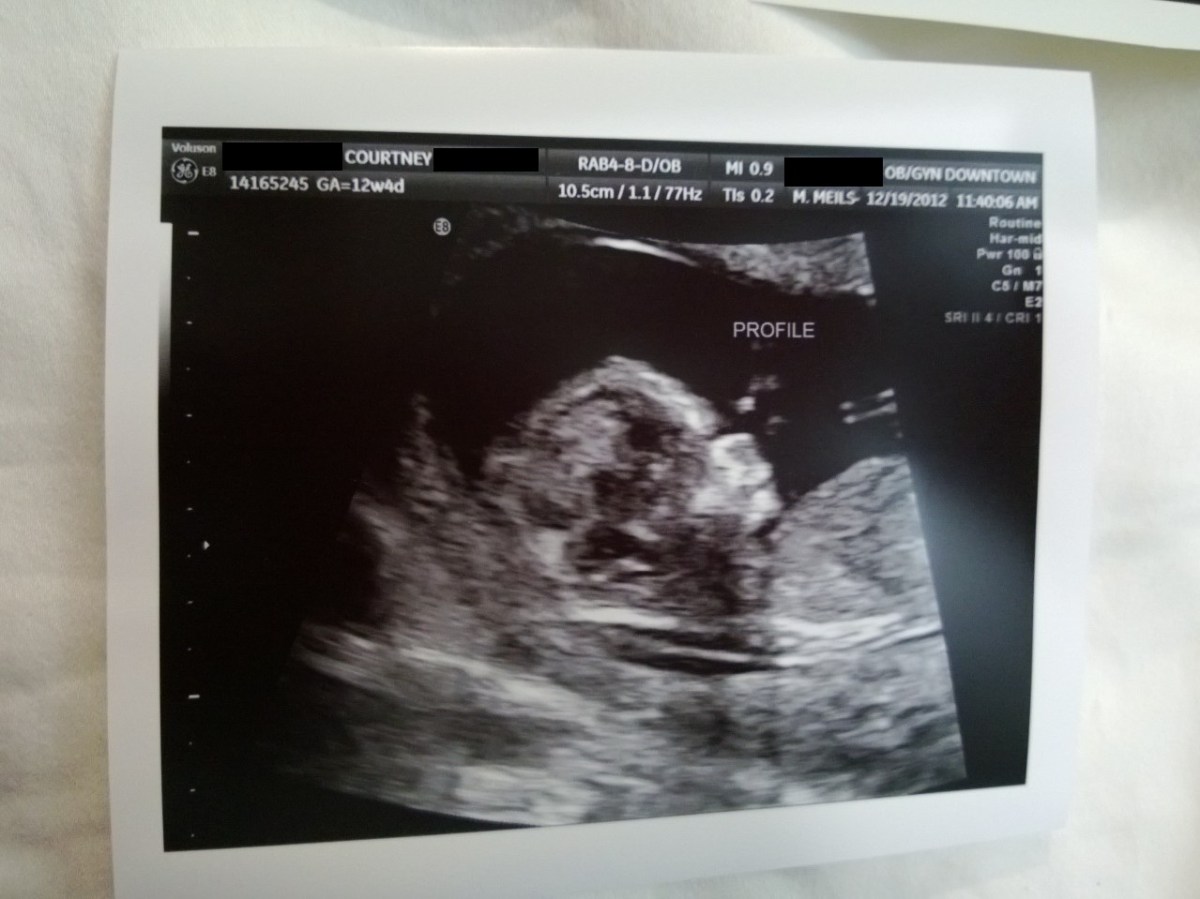

WP_20121219_012 December 27, 2012 by Courtney Leave a comment ← Previous Image Next Image → 12w4d Like Loading...